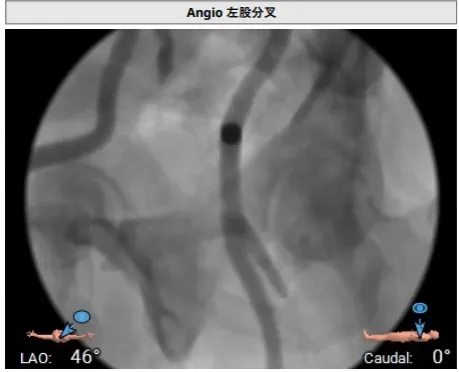

右侧股动脉分叉位置可

左侧股动脉分叉位置偏高

TAVR手术过程

TEER手术过程

建立右侧股静脉入路,在食道超声引导下进行房间隔穿刺,获得穿刺高度4.1cm,交换Super Stiff超硬导丝至左上肺静脉,使用血管鞘扩张股静脉后,沿超硬导丝送入可操控导引导管(SGC)至左房,将第一枚二尖瓣夹输送系统(CDS-XTR)送入左心房。送入夹子过程中为避免碰到左房组织完成Straddle“骑跨”,顺利完成Straddle并将夹子打弯至二尖瓣环水平。接下来为避免发生缠绕在1区进行轨迹测试,使夹子的运动轨迹指向心尖。在心房侧打开夹臂,调整夹臂方向指向12点-6点方位,与二尖瓣对合缘垂直。完成调整后将夹子移动至3区位置,将二尖瓣夹关紧后缓慢送入左心室。在左室打开夹子重新确认Orientation。准确成功捕捞3区前叶脱垂及反流区域,确认瓣叶瓣尖稳定插入夹臂后,Gripper Down,观察到明显Bouncing后,关紧夹臂予以夹合,夹子内侧反流消失,夹子外侧还有残余脱垂及中量反流。考虑瓣叶长度11mm以上,瓣口面积足够,决定在外侧Side by Side再植入一枚XTR,植入两枚XTR后活动稳固,反流降至Trace。术后肺静脉逆流消失,二尖瓣平均跨瓣压差2mmHg。

房间隔穿刺高度4.1cm

SGC穿房间隔进入左房

第一枚XTR进入左房

在1区进行轨迹测试和Orientation调整